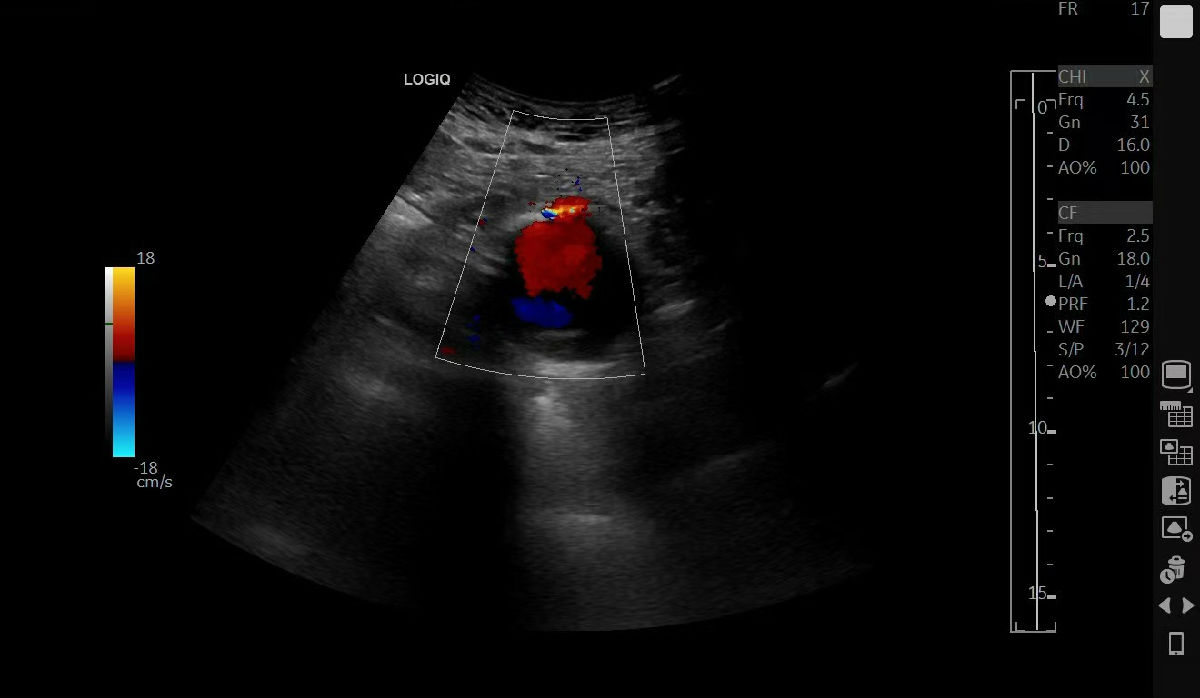

该患者因不明原因身体不适来我院就诊,超声医学科成为探查病情的“第一关”。腹主动脉夹层动脉瘤起病隐匿、进展凶险,诊断难度极高。科室团队凭借扎实的技术与丰富的经验,在细致检查中敏锐捕捉到可疑征象。为谨慎起见,医院迅速启动多学科会诊(MDT),超声医学科与医学影像科专家共同研判、交叉验证,最终明确诊断为腹主动脉夹层动脉瘤,为后续治疗争取了宝贵的“黄金时间”。

“此类疾病的救治,关键在于早发现、准判断。”超声医学科主任赵君智主任医师指出。超声以其无创、便捷、实时成像的优势,成为该病筛查与初诊的重要工具。此次精准诊断不仅为治疗提供了关键依据,也为后续向华西医院转诊搭建了扎实的沟通基础。鉴于病情复杂危重,我院在完成全面评估与稳定病情后,积极协助患者转至国内顶尖的四川大学华西医院进一步治疗。

此次患者返回我院超声医学科复查,超声显示支架位置精准、血流通畅,恢复情况理想。“当时真的非常害怕,多亏咱超声医学科的医生精准细致的检查,华西医院的专家又妙手解难,我才重获健康!”患者紧紧握住科室医护人员的手,激动地表示感谢。